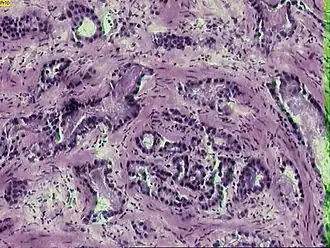

![]() Микрофотография инвазивной аденокарциномы простаты | |

Рак предста́тельной железы́ (рак проста́ты, карцино́ма проста́ты, карцино́ма предста́тельной железы́; англ. prostatic cancer, лат. adenocarcinoma prostatica) — злокачественное новообразование, возникающее из эпителия альвеолярно-клеточных элементов предстательной железы.

Около 95 % случаев рака предстательной железы составляют ацинарные аденокарциномы; на долю же остальных видов аденокарцином (протоковая, муцинозная, мелкоклеточная, переходно-клеточная) приходится не более 5 %[12]